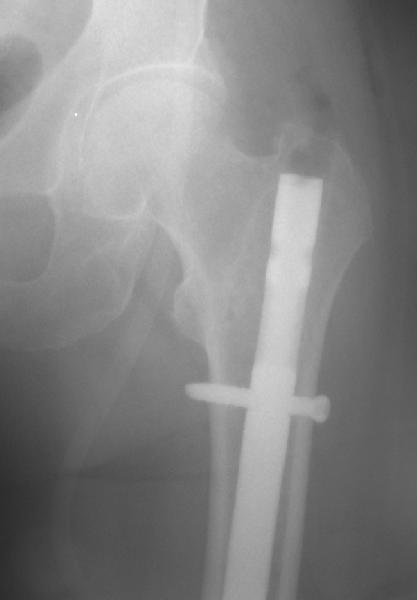

То, что планируется - наиболее распространенный подход. Еще менее инвазивный вариант - закрытый антеградный интрамедуллярный остесинтез. Мы используем гвозди, которые выпускаются предприятием ЦИТО, т.е. недорогие. Там в дистальное отверстие можно ввести 3 винта (2 снаружи и один навстречу), еще и угловая стабильность получается.

Больше 10 уже. Были 1 механическая неудача (сломалась очень тонкая ножка) и 1 глубокая инфекция.

Приходится индивидуально делать под конкретную ножку, с предпритием ЦИТО это получается за несколько дней и недорого.